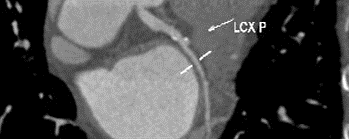

1.术前冠状动脉影像学评估:冠状动脉轻度粥样硬化累及多支,前降支中度狭窄,回旋支及右冠轻度狭窄。